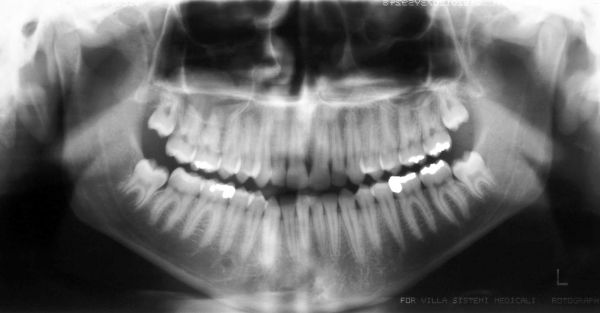

Panorâmica inicial